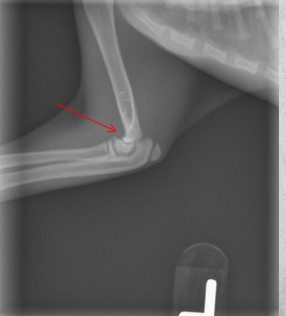

Mild widening of the left tibial apophyseal physis and small fragment visible at distal portion ->

tibial crest avulsion fracture of growth plate in 5m large breed dog

analgesia and hope it heals okay